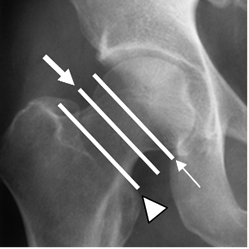

Fig 52. Clasificación de fractura extracapsular.

Rx AP. Fractura intertrocantérica (Flecha delgada) y subtrocantérica (Flecha gruesa).